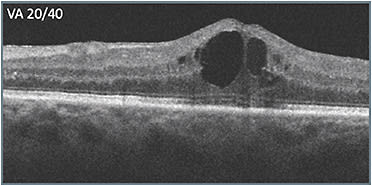

Unfortunately, the patient was unable to return for 10 weeks. When she did return, (C) her vision had worsened dramatically (20/150). In deciding what to do, the apparent progression of disease signs that had occurred over time (B & C) were considered. Retinal layer disorganization progressed, including what appeared to be signs of DRIL. More hyperreflective foci appeared as well, presumably indicating accumulation of exudate, including near the fovea. The decision was made to switch to a different class of therapy, which produced a favorable response (D). Vision improved from 20/150 to 20/60, and the retinal anatomy appeared as intact as it had been during the course of treatment.